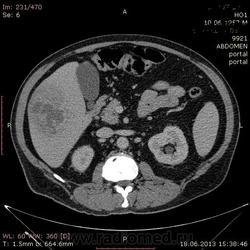

- https://radiomed.ru/sites/default/files/styles/case_slider_image/public/user/17529/img-0006-00001_2.jpg?itok=dK7FkYd5

На абсцесс похоже

На мой взгляд, абсцесс.

Тоже за абсцесс.

Cпасибо , коллеги.Сегодня больного прооперировали диагноз абсцесс правой доли печени.Оказывается больной когда - то получил тупую травму живота, об этом нам не говорил.....